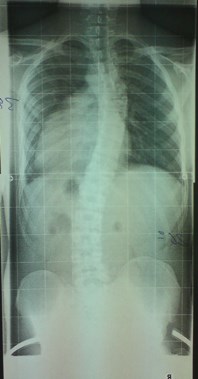

Das Röntgenbild vom November 2011 ist etwa 6 Wochen nach der Kur in Bad Salzungen geschossen worden. Mit 26° thorakal war das mein bester Wert, den ich je hatte. Leider bin ich dann wieder auf das Anfangsniveau von 34° thorakal zurück gefallen, trotz Korsett von cctec und ca. 120 Minuten Schroth-KG pro Woche. Ich muss dazu noch sagen, dass ich von Oktober 2010 bis November 2011 ein Korsett von Rahmouni getragen habe, allerdings nur etwa 8 Stunden am Tag, und die auch nicht am Stück. Das Korsett von cctec habe ich im Schnitt auch nur 8-10 Stunden pro Tag getragen. Aus privaten Gründen trage ich es seit Dezember 2013 nur noch sehr unregelmäßig, manchmal 3 Tage am Stück gar nicht, dann wieder 8 Stunden.

Röntgenbild vom August 2010 bei Dr. Hoffmann

August 2010 - Kopie.jpg (26.28 KiB) 9750 mal betrachtet

Röntgenbilder vom November 2011 und August 2013 bei Dr. Wilke

Vergleich 11-11 und 08-13 anonym.jpg (29.08 KiB) 9750 mal betrachtet